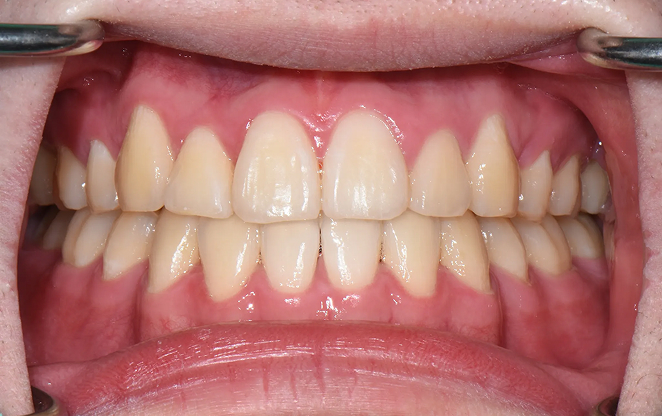

Before

After